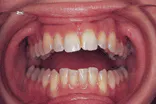

The problem: Intraoral examination revealed a large, diffuse lesion. The lesion appeared to be erosive and ulcerated.

The problem: Examination of the head and neck regions revealed enlarged superficial cervical and submandibular lymph nodes.

The problem: Intraoral examination revealed a swelling, and palpation of the area revealed a firm, nonmovable, solid tumor mass that measured approximately 25 millimeters in diameter.

The problem: The extraoral examination revealed on lesion that measured approximately 7 millimeters in diameter and exhibited a rolled and indurated border with a depressed, crusted center.

The problem: Oral examination revealed shiny gingiva with a lack of stippling in the area of involvement.